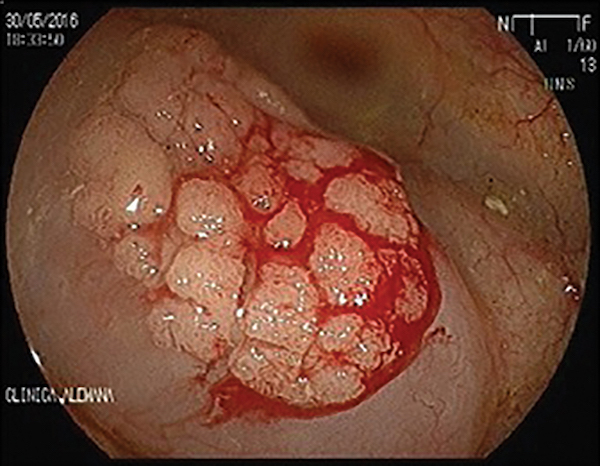

A 75-year-old man with a history of adenomatous polyps presented for a follow-up colonoscopy, 3 years after resection of 2 high-grade dysplastic adenomas. In the ascending colon, a 2-cm flat lateral-spreading tumor (LST), granular-type lesion was found [FIGURE A]. It was completely removed by en bloc endoscopic mucosal resection (EMR). There was prophylactic clipping of the EMR defect [FIGURE B]. No cancer was found in the resection specimen. Which of the following is true for this patient?

A. Prophylactic coagulation of the exposed superficial vessel in the EMR defect will decrease the incidence of delayed bleeding after EMR.

B. The patient should have annual stool-based surveillance by fecal immunochemical test (FIT).

C. The patient should have surveillance colonoscopy in 3 years.

D. The patient should have a right hemicolectomy.